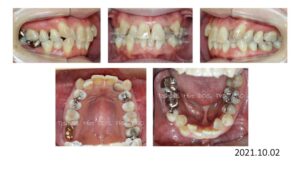

8歳の時、I市の歯科医院で、顎が狭くて歯が入りきらない、顎を拡げなければいけないといわれ、治療を開始したそうですが、6年経っても治療が終わらないどころか、写真のように全く噛み合っていないために、14歳の時にセカンドオピニオンで ひろ矯正歯科に来られました。

臼歯関係は、右が 4㎜ II級。左が 7㎜ II級で、7番しか咬合しておらず、著しい開咬を呈していました。

これは、拡大を始める前の写真ですが、口腔内写真を見る限り、拡大する必要はないです。

8歳からリンガルアーチで拡大を開始し、3年間拡大を続け、12歳でマルチブラケットを付けて治療を開始したそうですが、開咬が治らないためにアンカースクリューを4本打って治療を続けたとのことです。

こんなスクリューじゃあ何の意味もありません。

まさにやっている事がデタラメです。

ひろ矯正歯科に来られた時には、口腔内清掃状態は悪く、全ての歯が齲蝕でボロボロ、要治療でした。

治療中はブラッシング指導は一切無かったそうです。

検査、診断の結果、この患者さんは矯正のみで治療することは不可能、上下顎骨の離断が必要で外科矯正となりました。

この患者さんも歯が入らないから、顎を拡げましょうと言われ拡大を続けましたが、治療前の状態をみると、判断を誤っていることがわかります。